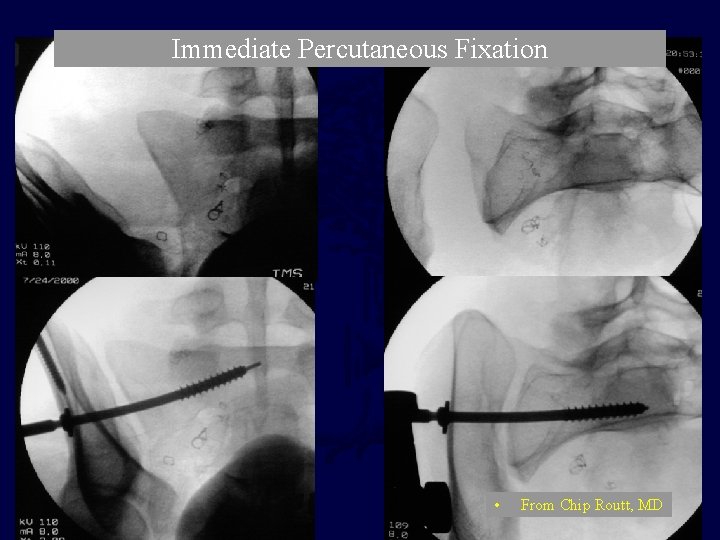

Immediate Percutaneous Fixation • From Chip Routt, MD